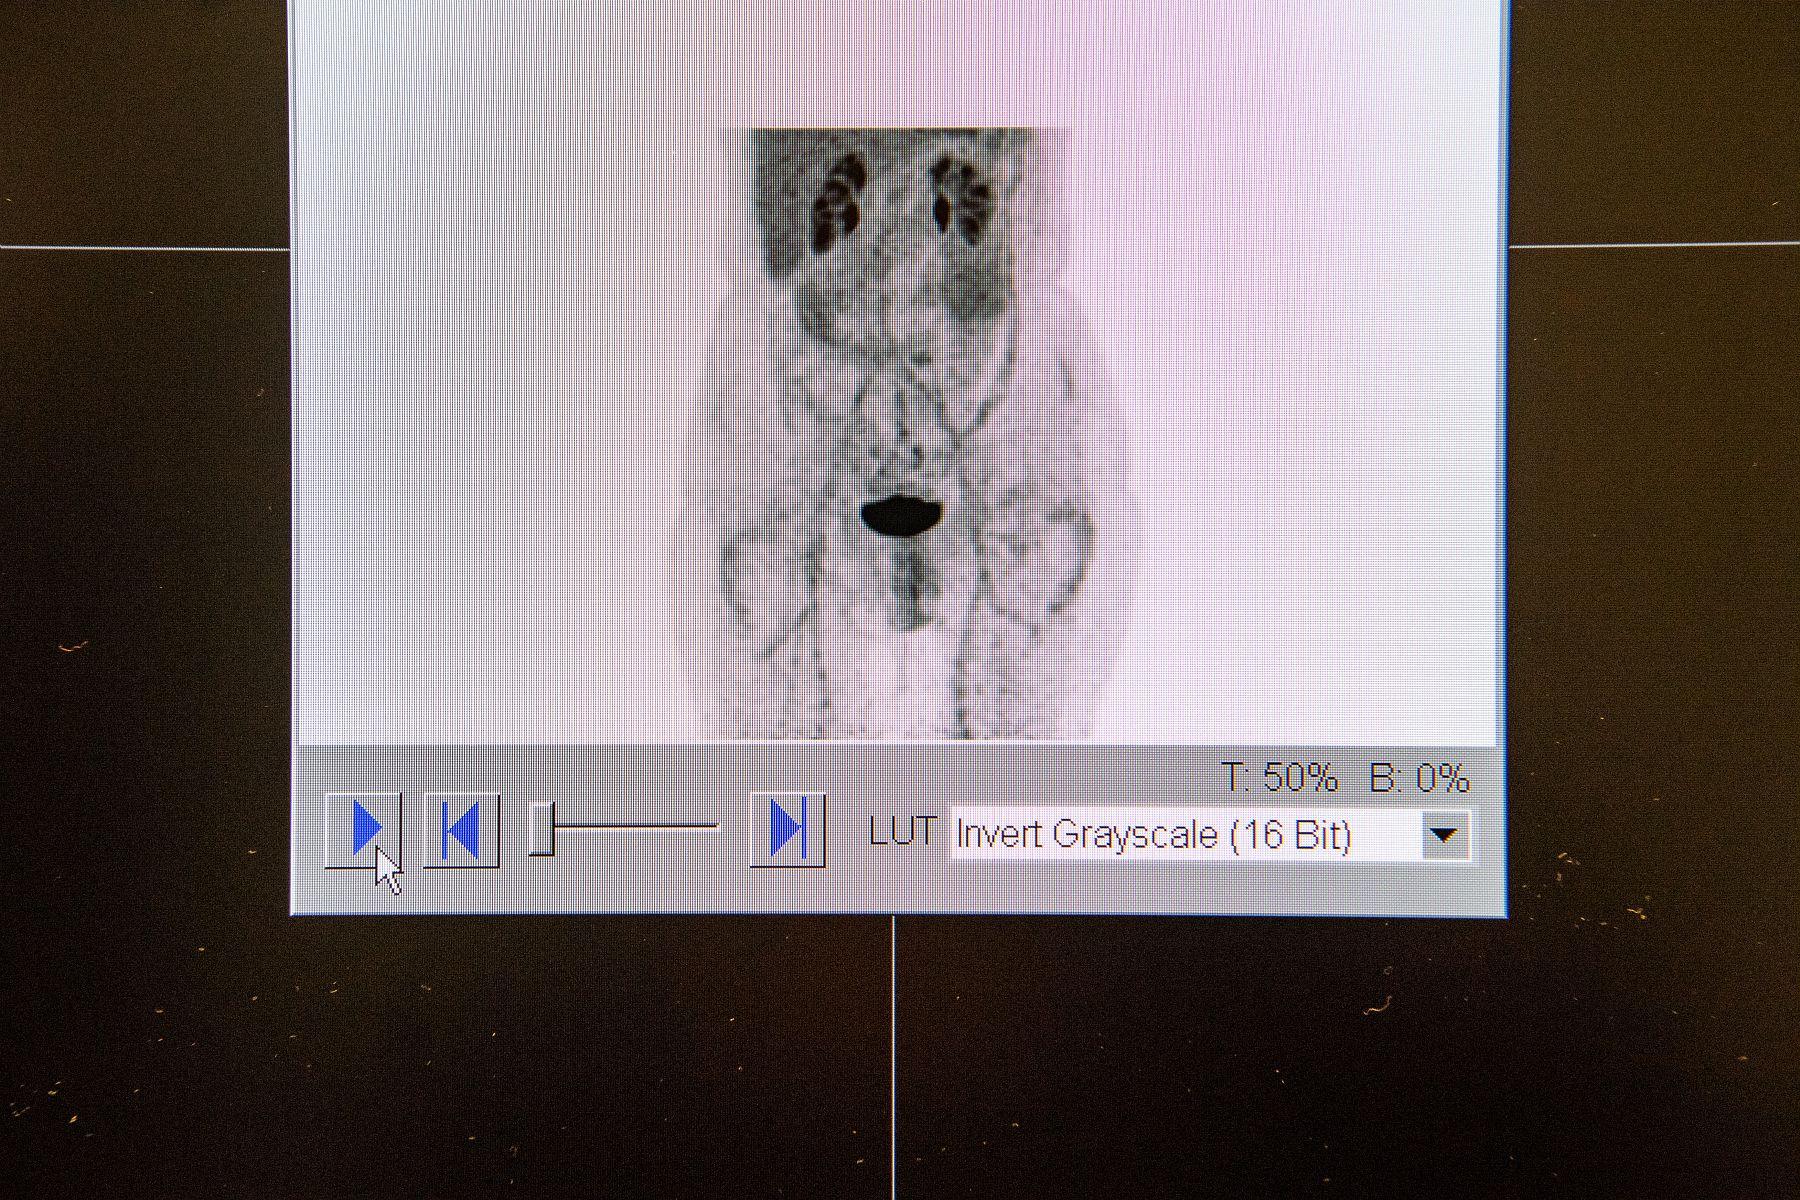

La course lente du tramway s’arrête devant le bâtiment flambant neuf du Centre hospitalier régional d’Orléans (Loiret). Depuis 2015, ses locaux vastes et colorés abritent de nouveaux équipements en médecine nucléaire. C’est ici que nous attend Gilles Le Rouzic, physicien médical : « Les examens d’imagerie utilisant les rayonnements ionisants sont de plus en plus prisés, relève-t-il. La tomographie par émission de positons [TEP] a révolutionné le suivi des patients en cancérologie. » L’injection aux patients de glucose « marqué » par un atome de fluor radioactif permet de repérer les cellules les plus actives, comme les cellules tumorales. Cette image fonctionnelle est superposée à celle, anatomique, d’un scanner à rayons X réalisé par la même machine dans le même temps d’examen, pour repérer où siègent les cellules tumorales. De tels examens d’imagerie sont régulièrement réalisés au cours de la prise en charge des patients. S’ils facilitent le traitement, ils contribuent aussi à l’accumulation des doses dues aux rayonnements.

Professionnel titulaire du diplôme de qualification en physique radiologique et médicale (DQPRM), le physicien médical a pour mission de paramétrer les appareils et d’optimiser les protocoles. Dans une grande salle climatisée, Gilles Le Rouzic nous présente le TEP-TDM – communément appelé PET-scan – de dernière génération acquis par l’hôpital. Un investissement d’environ 1,7 million d’euros qui procure une meilleure qualité d’image, sans irradier davantage et avec des temps d’examen réduits.

Le scanner de ce TEP-TDM est capable de fournir des images de qualité, au prix d’une dose importante pour le patient. « Comme il n’existe pas de NRD pour ces examens, nous avons mis en place une méthode permettant de diviser par trois les niveaux dont nous disposons pour les scanners diagnostiques », se félicite le physicien.

Image d'une tomographie "basse dose" en cours de reconstruction par l'appareil TEP-TDM (tomographie par émission de positon couplée à un tomodensitomètre à RX). La nouvelle caméra a permis de réduire l’exposition des patients tout en conservant une bonne qualité d’image.